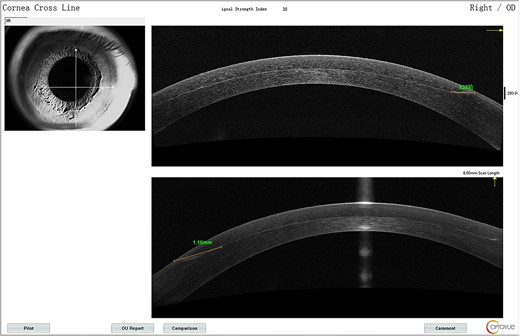

The VA in the patient’s left eye exhibited a marked decrease, from an initial measurement of 20/25 on Day 12, to 20/50 just a day later. Concurrently, the VA in the right eye remained 20/70 on Day 13. Distinct interface lesions were observed in the nasal inferior quadrant of both eyes, spreading radially toward the pupil and originating at the lower edge of the corneal flap. This pattern was consistently observed over the 13-day monitoring period for both eyes (Fig. 3). On AS-OCT, the lesions were seen to enlarge in extent, elongating up to 2.32 mm toward the pupil by Day 13, exhibiting a higher level of reflectivity (Fig. 4).

(A) AS-OCT signs for the right eye on the fifth day; (B) a detailed shot of the nasal inferior quadrant region.